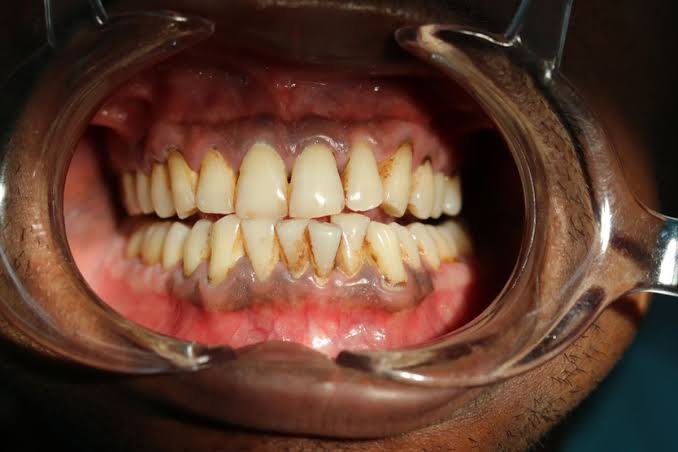

Gusi Hitam adalah kondisi perubahan warna jaringan gusi menjadi cokelat tua, abu-abu, atau hitam. Perubahan warna ini bisa terjadi secara alami maupun akibat faktor tertentu, mulai dari kebiasaan sehari-hari hingga masalah kesehatan mulut yang serius Gusi Hitam.

Tidak hanya itu, penumpukan plak dan karang gigi akibat kebersihan mulut yang buruk juga bisa membuat gusi tampak gelap. Infeksi gusi atau radang gusi (gingivitis) bahkan dapat berkembang menjadi penyakit periodontal jika tidak segera di tangani.

Gusi hitam yang normal biasanya tidak disertai keluhan lain. Namun, jika muncul gejala tambahan seperti gusi mudah berdarah, nyeri, bengkak, bau mulut kronis, atau gigi terasa goyang, maka kondisi tersebut perlu segera di periksa.